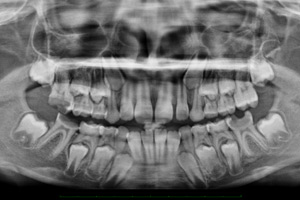

Ortopantomografia Digital

O paciente posiciona-se no ortopantomógrafo, imóvel enquanto são emitidos os Raios X movendo-se para tal o ortopantomógrafo em torno em torno do paciente (arcadas dentárias). Este exame é sempre feito por um técnico de radiologia podendo ou não ter a intervenção de um Médico (Radiologista, Dentista ou Estomatologista).